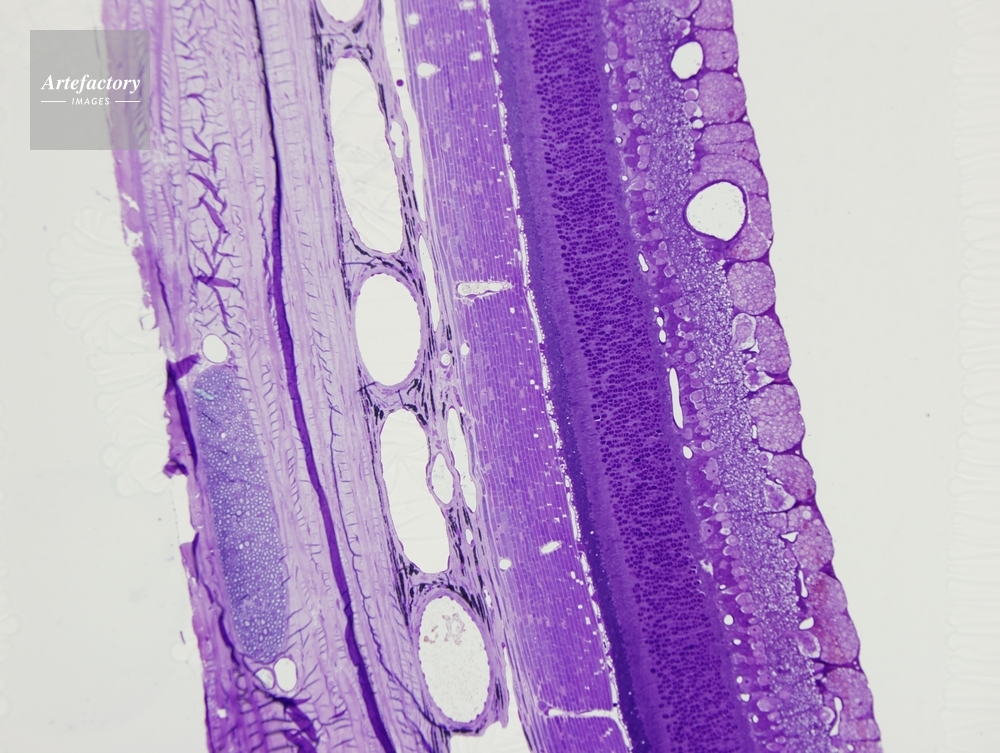

| 作品タイトル | ネコ,網膜 | モデルリリース | なし | |

| 作家 | OLYMPUS CORPORATION Technolab | プロパティリリース | なし | |